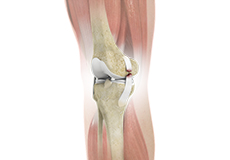

Knee Cartilage Restoration

Knee cartilage restoration is a surgical technique to repair damaged articular cartilage in the knee joint by stimulating new growth of cartilage or by transplanting cartilage into areas with defects in order to relieve pain and restore normal function to the knee.

High Tibial Osteotomy

High tibial osteotomy is a surgical procedure performed to relieve pressure on the damaged site of an arthritic knee joint. It is usually performed in arthritic conditions affecting only one side of your knee and the aim is to take pressure off the damaged area and shift it to the other side of your knee with healthy cartilage.